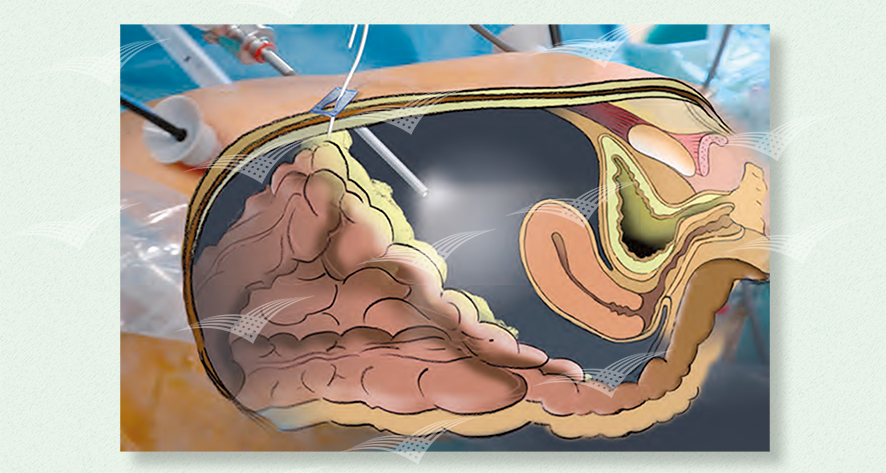

Laparoskopisches Gewebe Retraktionssystem T’Lift

T’Lift fixiert selbständig bis zu 1 kg und benötigt keinen eigenen Trokarzugang